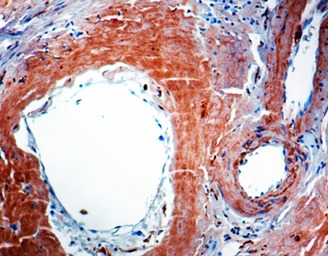

IHC-P analysis of human amyloidosis tissue using GTX27501 beta Amyloid (1-40) antibody [BAM-10].